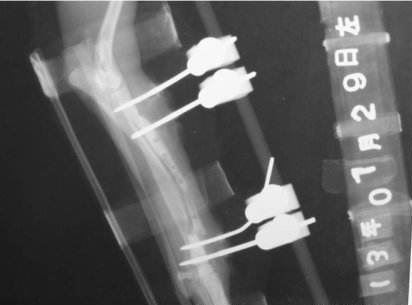

![]() Qhov kev kho sab hauv yog txhawm rau kho thiab kho cov pob txha lov nrog cov phiaj hlau thiab cov ntsia hlau hauv qab qhov muag pom ncaj qha. Kev kho sab nraud yog tsim los ntawm kev siv tshuaj pleev ib ce plaster thiab txaws. Qhov chaw tawg yog thaj chaw nyob sab nraud kom ruaj khov kho kom ruaj khov, thiab tus txhim kho sab nraud siv lub stent ruaj ruaj los tsav lub ntsia hlau tshwj xeeb rau hauv cov pob txha kom ua tiav kev ruaj khov. |

Cov ntaub ntawv raw khoom siv los ua tus kho kom zoo sab nraud tsis tsuas yog ua tau raws li cov kev ua haujlwm yooj yim ntawm kev kho, kho qauv, thiab nias ntawm tes, tab sis kuj tseem pab txhawb kev kho pob txha lov. Kev teeb tsa, ntim, nyhav thiab yoog raws kuj tseem ceeb. Feem ntau, cov khoom siv raw nrog kev kho kom zoo tuaj yeem ua tiav qhov kev kho kom zoo ntawm cov pob txha qub, tab sis qhov kev ntxhov siab los tiv thaiv kab mob tsis yog qhov muaj txiaj ntsig rau qhov tsim los ntawm sab nraud epiphysis. Lub pob txha tawg kho feem ntau yuav tsum tau nyob ntev ntev, thiab nws tau raug mob thib ob, yog li cov neeg kho sab nraud nyob hauv cov khoom siv. Cov ntaub ntawv zoo nrog lub zog zoo, lub teeb nyhav thiab X-ray kis yuav tsum tau siv. |

![]() Tsoos pob txha sab nraud fixers Cov tsoos pob txha sab nraud kho cov khoom siv feem ntau yog ua los ntawm cov khoom siv hlau, xws li titanium alloy, cobalt chromium molybdenum alloy, thiab lwm yam. Cov txheej txheem elastic ntau dua 100 GPa, tab sis tib neeg cov pob txha elastic modulus feem ntau tsuas yog 1-3 GPa, thiab ntau dhau heev elastic modulus yog kev nrhav. Kev ntxhov siab loj heev occlusion yog tsim, yog li cov khoom siv sib txuas uas yog siab me ntsis thiab muaj qhov qauv zoo ntawm elasticity yog qhov ntau tsim nyog. Kev siv cov roj carbon fiber ntev ntev PEEK cov khoom siv sib ntxiv hloov cov khoom siv txho lossis cov hmoov carbon fiber ntxiv tiv thaiv cov khoom siv kom ua rau cov khoom siv sab nrauv sai muaj ntau qhov zoo tshaj qhov thov muaj txiaj ntsig ntawm kev hnav tsis kam. | ![]() PEEK Carbon Fiber Pob Txha Sab Nraud Fixator bracket Polyetheretherketone (PEEK) muaj qhov muaj tsawg tsawg, kev ua haujlwm zoo, hydrolysis tsis kam, tiv taus corrosion, nplaim taws rov qab thiab rwb thaiv tsev. PEEK cov khoom siv yog tsis muaj tshuaj lom thiab lub teeb hauv qhov hnyav, thiab yog cov khoom siv ze tshaj plaws rau tib neeg cov pob txha. Kev sib xyaw ua ke ntawm lub cev, tab sis nws cov tawv thiab kev cuam tshuam lub zog sib txawv, thaum ua ke nrog kev txhawb nqa cov roj carbon fiber ntau, nws cov cuab yeej muaj zog yuav nce siab, qhov hnav tus nqi thiab kev sib txhuam coefficient ntawm cov khoom kuj tseem yuav txo, ntxiv rau, qhov kev ua tau zoo ntawm cov khoom siv sib xyaw ua ke tuaj yeem tsim Cov cuab yeej kuj tuaj yeem ua kom tau ntau yam ntawm cov kev ua kom nruj txhawm rau hauv ntau, thiab feem ntau ua kom pom kev zoo thermal stability, tiv taus corrosion, lub teeb nyhav, hluav taws xob zoo electromagnetic hluav taws xob, thiab zoo interface ntawm PEEK thiab carbon fiber, carbon fiber Cov. Lub zog PEEK txhawb kev ua kom tau zoo nyob rau hauv qhov chaw tiv thaiv tsis kam, thaum tshav kub kub thiab cov av noo tsis kam, kev laus tiv thaiv thiab kev cuam tshuam. |